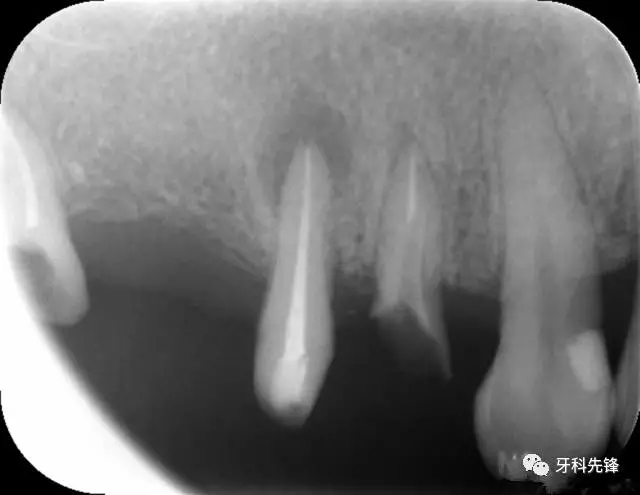

圖1 術前X光片

640.webp.jpg

X 示:15  根管透射,根尖有陰影

14  根管阻射,恰填,無異常

46  根管阻射,恰填,根分叉骨密度降低,近中根尖陰影較大

圖8治療術后X光片

640.webp (10).jpg